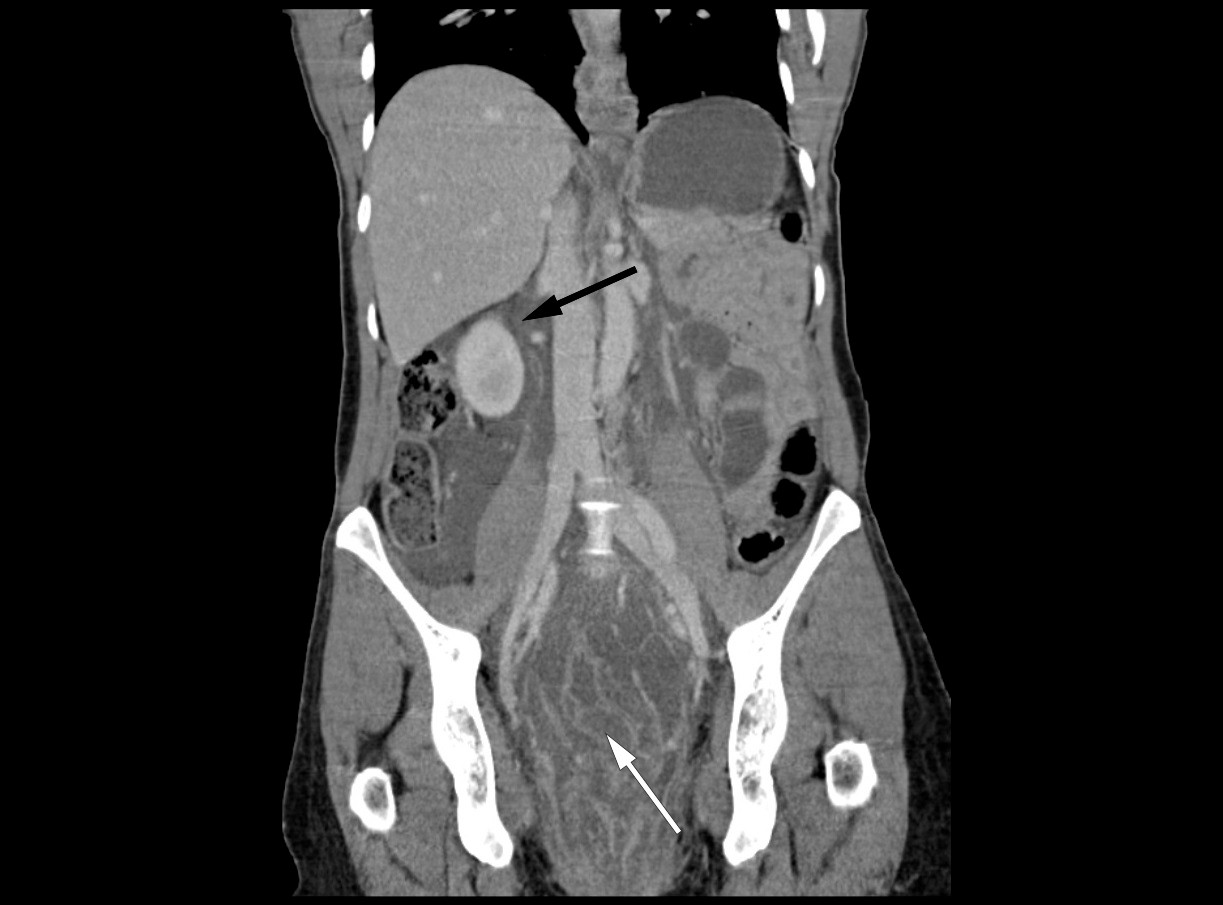

Knapt to timer etter innleggelsen ble det utført CT av thorax, abdomen og bekken med intravenøs kontrastvæske. Det ble ikke gitt peroral eller rektal kontrast. I thorax ble det ikke påvist noen aktuell patologi. CT av bekken viste en uttalt ødematøst fortykket rektumvegg på opptil 2 cm, fra sigmoidovergangen i promontorienivå til anus. Det var ikke patologisk gass i bløtvevet, men et mesorektalt ødem som strakte seg sammenhengende retroperitonealt til nyrevenenivå. Det var moderat mengde fri væske i peritonealhulen i nedre abdomen og bekken. I peritoneum var det ingen fri luft. Parenkymatøse organer og genitalia interna var uten funn. Sigmoideoskopi viste proktittforandringer med ødematøs slimhinne og rubor i distale 10 cm av rektum. Det var ikke tegn til tarmperforasjon eller tarmiskemi.

På grunn av klinisk forverring uten respons på igangsatt behandling og mistanke om abdominalt infeksjonsfokus, ble det gjort laparotomi. Man fant rikelig ascites i bukhulen og retroperitonealt ødem fra øvre nyrepol på begge sider som strakk seg ned i bekkenet og mesorektum. Det var ingen tegn til intraabdominale abscesser eller tarmperforasjon. Funnene var ikke forenlig med nekrotiserende fasciitt, idet man fant viabelt vev uten tegn til gassdanning, krepitasjoner eller henfall. Det ble gjort reseksjon av colon sigmoideum og rektum ned til analkanalen med anleggelse av endekolostomi. Retroperitoneum ble åpnet og drenert for væske. Det ble tatt bakteriologisk undersøkelse av ascites og retroperitonealvæsken. Buken ble midlertidig lukket med vakuumbandasje, slik at vi senere kunne gjøre en ny vurdering. Etter å ha konferert med infeksjonsmedisiner ble antibiotikabehandling endret til meropenem 1 g × 3 intravenøst for å oppnå bedre penetrans til bløtvev.

Hos vår pasient viste CT av buken omfattende ødem perirektalt og retroperitonealt. Sigmoideoskopi viste proktitt. På bakgrunn av dette mistenkte man primært en gramnegativ infeksjon og opererte pasienten med rektumreseksjon med distal avsetting helt ned på analkanalen. Direkte mikroskopi av ødemvæsken burde vært gjort under primærinngrepet, da påvisning av streptokokker trolig ville medført at man gjorde analamputasjon ved primæroperasjonen for å sanere inngangsporten for infeksjonen. Sigmoideum var ødematøs og betent og måtte recesseres. Direkte mikroskopi under primærinngrepet ville ikke påvirket denne avgjørelsen eller omfanget av reseksjonen.